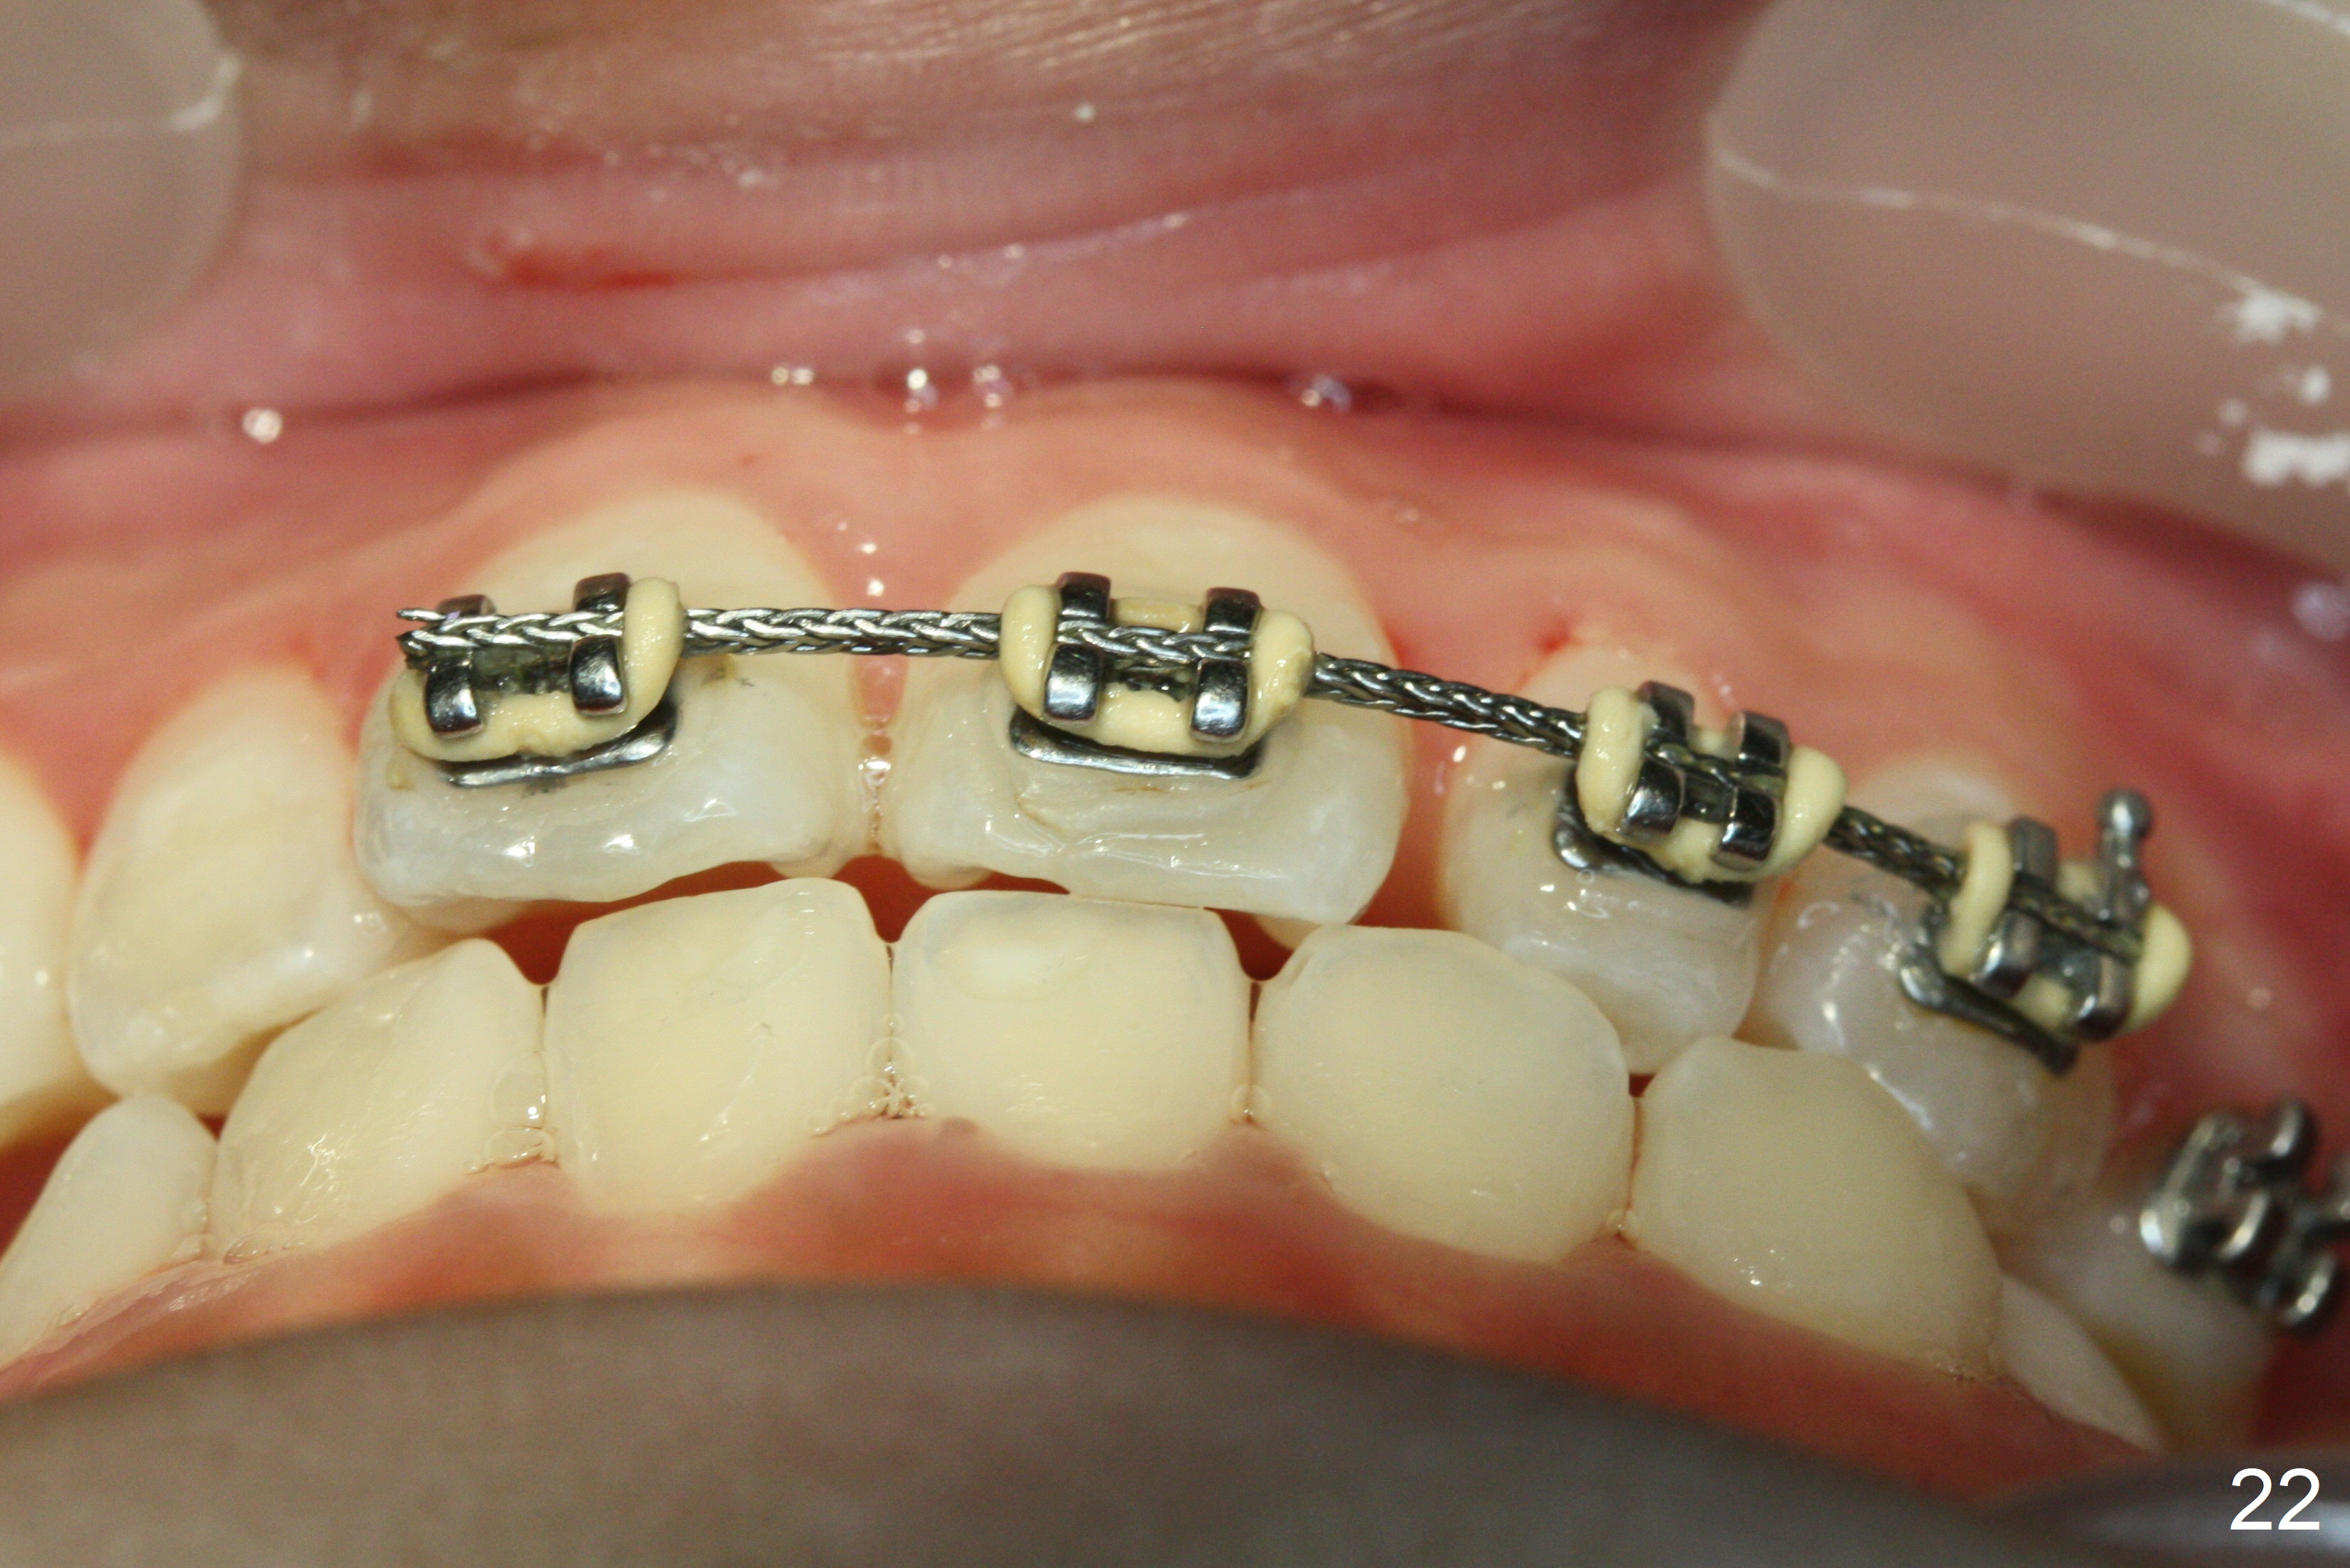

OK Xin, just evaluated the case. If she started with the anterior dental crossbite and you are barely over-corrected right now, I would be very comfortable discontinuing treatment. At her age, there is nothing that can no longer be dealt with beautifully when it is more age appropriate.When anterior cross bite is corrected 19 months post banding, the tooth #10 (microdontia) has tendency of edge-to-edge (Fig.16,17). Power chains are used to create space for #11 to erupt fully before bracketing. In spite of the effort, the peg lateral remains edge-to-edge 23 months post banding (Fig.18,19). The segmental 19x26 braided wire retains as a retainer to prevent #10 from cross bite. The facial profile is more or less normal immediately post debracketing (Fig.20). The anterior occlusion appears to remain basically the same 7 months post debracketing (Fig.21,22). UR3 erupts, while the diastema mesial to UL2 enlarges so that the arch wire appears shorter. UL2,3 appear to be in cross bite 14 months post debracketing, while Es retain at the age of 13 (delayed development, Fig.23).